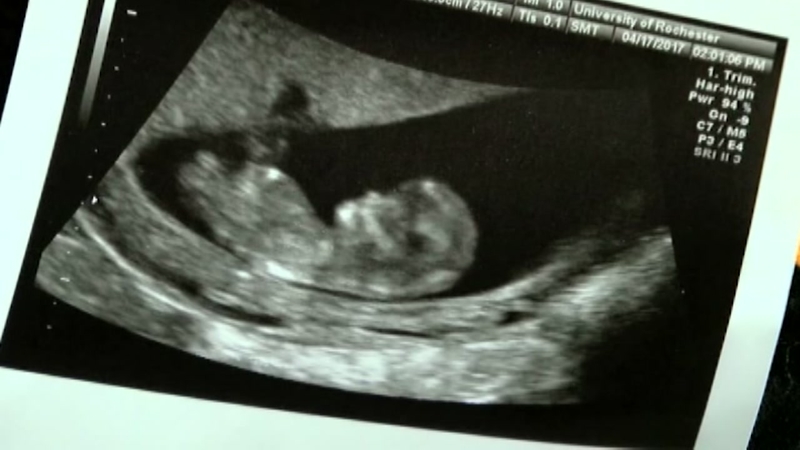

ΑΠΕΙΚΟΝΙΣΗ ΑΥΤΟΜΑΤΗΣ ΕΚΤΡΩΣΗΣ

• Εξέταση με υπερήχους για τη βιωσιμότητα του εμβρύου και τον αποκλεισμό έκτοπης κύησης

• Η απεικόνιση με υπερήχους μπορεί να είναι αρκετά ακριβής ώστε να επιβεβαιώσει μια ενδομήτρια κύηση στην 4η ή 5η εβδομάδα της κύησης.

• Δύο θετικά σημεία πρώιμης κύησης είναι η ταυτοποίηση (αναγνώριση) των καρδιακών ήχων του εμβρύου (συνήθως πραγματοποιείται με μηχανήματα Doppler κατά ή μετά την 9η εβδομάδα της κύησης) και η αναγνώριση των εμβρυϊκών μελών (τμημάτων) στον αμνιακό σάκο με τους υπερήχους.